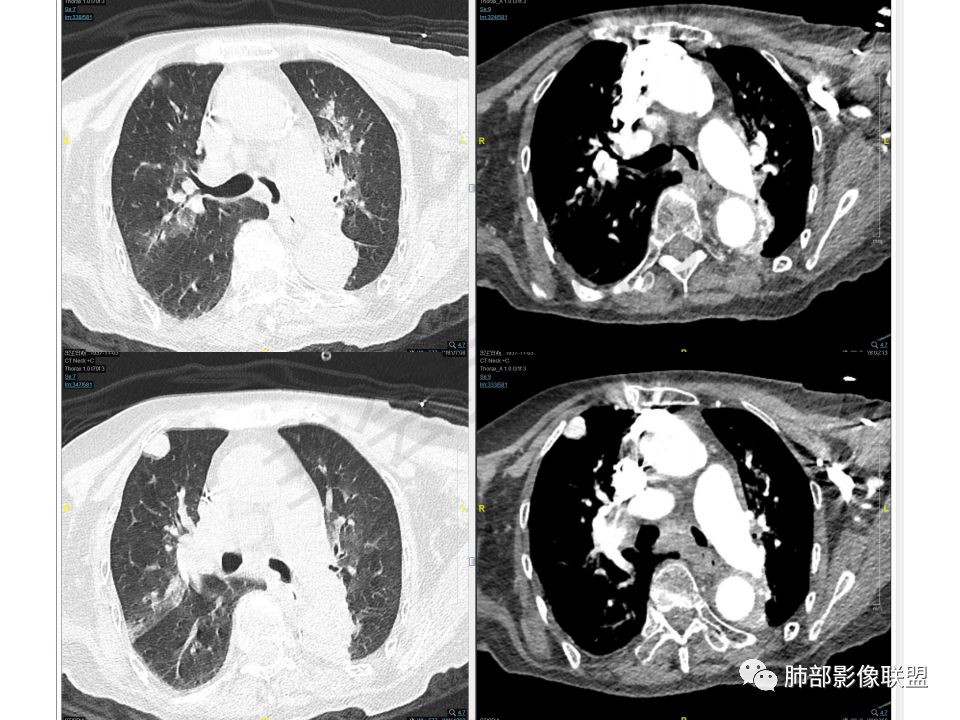

老年女性,两肺多发球形结节,边缘光滑,部分位于胸膜下,纵隔淋巴结肿大不明显,胸水少量,增强后强化明显,考虑转移,肉瘤转移的可能,补充下病史。气管内新生物,是不是二元,息肉或肿瘤

老年女性,间断咯血两年。影像:气管内带蒂结节,边缘光滑明显强化。左肺下叶背段支气管截断,远端不张。两肺散在大小不等结节及磨玻璃影,明显强化,磨玻璃影考虑合并出血可能。纵隔多发淋巴结肿大,两侧支气管受压。综合考虑:肺癌伴两肺转移。原发气管结节还是左肺下叶背段?腺样囊性癌?类癌?

气管占位,两肺多发肿块,左下肺不张。

气管占位与肺内肿块血供异常丰富,接近大动脉强化,可以考虑同源

而血供丰富的转移瘤不多,常见于甲状腺癌,肾透明细胞癌,肉瘤及少数腺癌。没给平扫,不知道有没有钙化,钙化常见于甲状腺癌及成骨类的肉瘤。

老年女性,慢性病程。两肺多发类圆形结节、肿块,边缘光滑,胸膜下分布为主,显著强化,考虑转移瘤。气管内肿块,边缘光整,强化方式与肺内肿块一致,一元考虑气管肉瘤并双肺转移。

双肺多发大小不等结块,边缘光滑,随机分布,部分融合,密度不均匀,增强后可见不均匀明显强化(富血供),肺门及纵隔淋巴结肿大融合,老年女性,综合考虑转移瘤,建议查全身脏器,必要时Pet-CT, 鉴别小细胞肺癌。

老年女性,气管腔内占位,左肺下叶阻塞性炎症伴不张,腔外病灶大于腔内,左肺门血管包埋,外缘欠光滑,似有冰山征。纵隔淋巴结,双肺多发富血供团块样转移结节。

老年女性,病史2年,以咯血丶贫血为主,CT:气管内带蒂肿物丶双肺多发球型团块与结节,明显强化丶程度一致,故考虑同源,富血供。纵隔7组淋巴结肿大,脂肪间隙不清。

晨读:老年女性,间断咯血2年,呼吸困难2月,加重3天,高血压冠心病史40余年,阵发性房颤20余年,老年痴呆10年,贫血5年,气管腔内不规则结节,强化明显,双肺多发圆形或类圆形结节,强化明显。临床症状病史加影像改变综合分析,有三种可能:1、气管原发恶性肿瘤伴肺内转移,2、气管与肺部均为富血供转移,原发待定,3、气管内良性肿瘤性结节,肺内恶性转移。个人倾向于气管类癌或非典型类癌合并肺上转移,并类癌综合征可能,其他两个可能待鉴别,建议查甲状腺,腹部CT,肿瘤标志物。